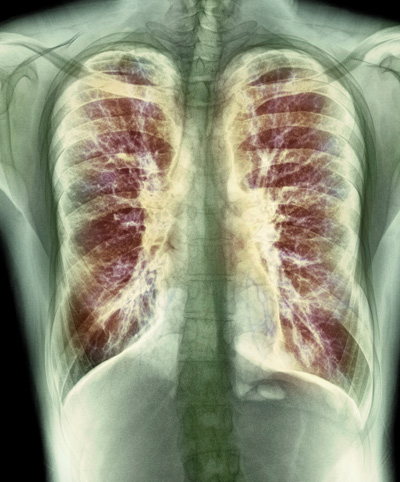

Røntgenbilde av ung mann med cystisk fibrose. Illustrasjonsfoto: Sciencephoto/NTB scanpix